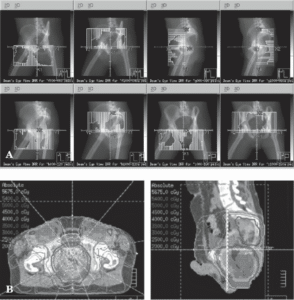

IMRT (شکل 24.3) و SBRT دوز تابشی را ارائه میدهند که نسبت به دوز تابشی که با روشهای مرسوم ارائه میشود، دقیقتر با تومور مطابقت دارد. هر دو IMRT و SBRT شامل برنامهریزی معکوس هستند. متخصص پرتودرمانی، هدف تومور، هرگونه هدف گرهای منطقهای و اندامهای در معرض خطر آسیب تابشی را در سیتیاسکن مشخص میکند. سپس، کامپیوتر توزیع دوز را در چارچوب محدودیتهای دوز بافت طبیعی که متخصص پرتودرمانی مشخص کرده است، بهینه میکند. در IMRT، پرتو تابش به صدها پرتو کوچک تقسیم میشود که روشن و خاموش میشوند و در نتیجه توزیع دوز بسیار سفارشی ایجاد میشود. این شکل از برنامهریزی و تابش پرتو به ویژه برای پرتودرمانی تفکیکشده مفید است که در آن میتوان دوزهای بالای تابش را در حالی که ساختارهای حیاتی محافظت میشوند، تاباند.

![]() |

| شکل 24.3 پرتودرمانی با شدت تعدیلشده (IMRT) امکان حفظ بهینه بافتهای طبیعی و امکان کنترل بهتر تومور موضعی با استفاده از دوزهای بالاتر تابش را فراهم میکند. IMRT برای سرطان مقعد یکی از بهترین کاربردهای این درمان است. IMRT اندام تناسلی را حفظ میکند، در نتیجه سمیت را کاهش میدهد و عملکرد جنسی را در درازمدت بهبود میبخشد. میدانهای درمانی (A) و دزیمتری (B) برای یک طرح IMRT معمولی نشان داده شده است. |